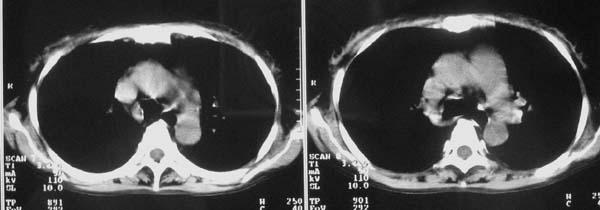

以下是引用zjzjr在2007-9-20 12:29:00的发言:[br]双肺磨玻璃改变,考虑肺水肿.

以下是引用yangzongshan在2007-9-20 18:29:00的发言:[br]两肺毛玻璃样改变,其内可见肺纹理影,无胸腔积液,故考虑肺泡蛋白沉积症

以下是引用276894491在2007-9-20 13:40:00的发言:[br]考虑肺水肿;外源性过敏性肺炎不排除。

以下是引用逸风在2007-9-20 20:45:00的发言:[br]两肺磨玻璃样改变,临床病史短,发热,考虑病毒感染合并右肺代偿性肺气肿.待排肺水肿,病史短,不支持肺泡蛋白沉着症.